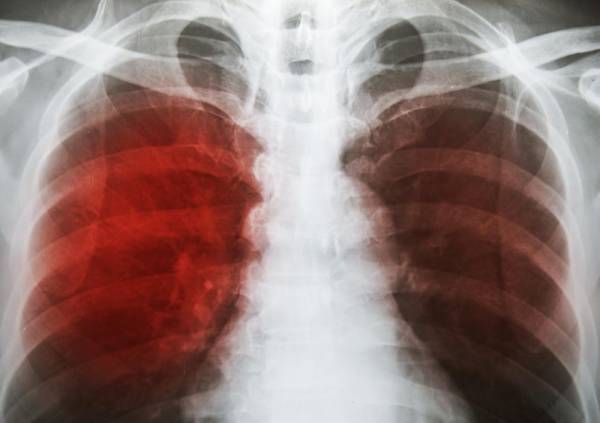

ستجري إتاحة علاج جديد من 3 أدوية لمرض السل في 150 دولة منها الهند وجنوب إفريقيا بسعر 1040 دولارا للجرعة الكاملة (3900 ريال)، أي أكثر من ضعف التكلفة المقترحة في السابق من خلال منظمات صحية تقدم علاجات أخرى. وقالت شراكة مكافحة السل التابعة للأمم المتحدة إن العلاج BPaL ستحصل عليه الدول المؤهلة عن طريق جلوبال دراج فاسيليتي، وهي مورد عالمي لعلاجات السل تأسس في عام 2001 للتفاوض على خفض أسعار العلاج. وتسبب السل في وفاة 1.5 مليون شخص في 2018. وعلاج (بي.بي.إيه.إل) يُتناول عن طريق الفم ويعد بفترة علاج أقصر وأكثر ملاءمة من العلاجات المتاحة الآن التي تستخدم مزيجا من المضادات الحيوية خلال فترة زمنية تصل إلى عامين. أما المزيج الجديد فيعالج سلالات المرض الأكثر مقاومة للأدوية ويتكون من دواء بريتومانيد الذي أقره مؤخرا تحالف السل، بالإضافة إلى دواء لاينزوليد ودواء بداكيلين الذي تنتجه جونسون آند جونسون. والبريتومانيد الذي سيتوفر بسعر 364 دولارا لفترة علاجية كاملة هو ثالث دواء جديد للسل المقاوم للعقاقير يجاز خلال 40 عاما بعد بداكيلين وديلامانيد. وتنتقد المنظمات المعنية بالصحة منذ فترة طويلة تكلفة بداكيلين وديلامانيد. وشنت منظمة أطباء بلا حدود حملة مستمرة وعلنية بشأن جونسون آند جونسون بسبب سعر 400 دولارا، الذي تباع به الجرعة العلاجية الكاملة التي تستمر ستة أشهر من بداكيلين. وقالت المنظمة إن بداكيلين يمكن إنتاجه وبيعه بربح 25 سنتا يوميا، وإن سعر مزيج العلاج الكامل للسل المقاوم للعقاقير يجب ألا يزيد على 500 دولار. لكن شراكة مكافحة السل تقول إن تكلفة علاجات أخرى للسل المقاوم بشدة للعقاقير تتراوح بين ألفين وثمانية آلاف دولار لفترات علاجية تدوم 20 شهرا على الأقل. وقالت شراكة مكافحة السل إنها ستبدأ في توريد الجرعات باتباع إرشادات منظمة الصحة العالمية بشأن استخدامه.